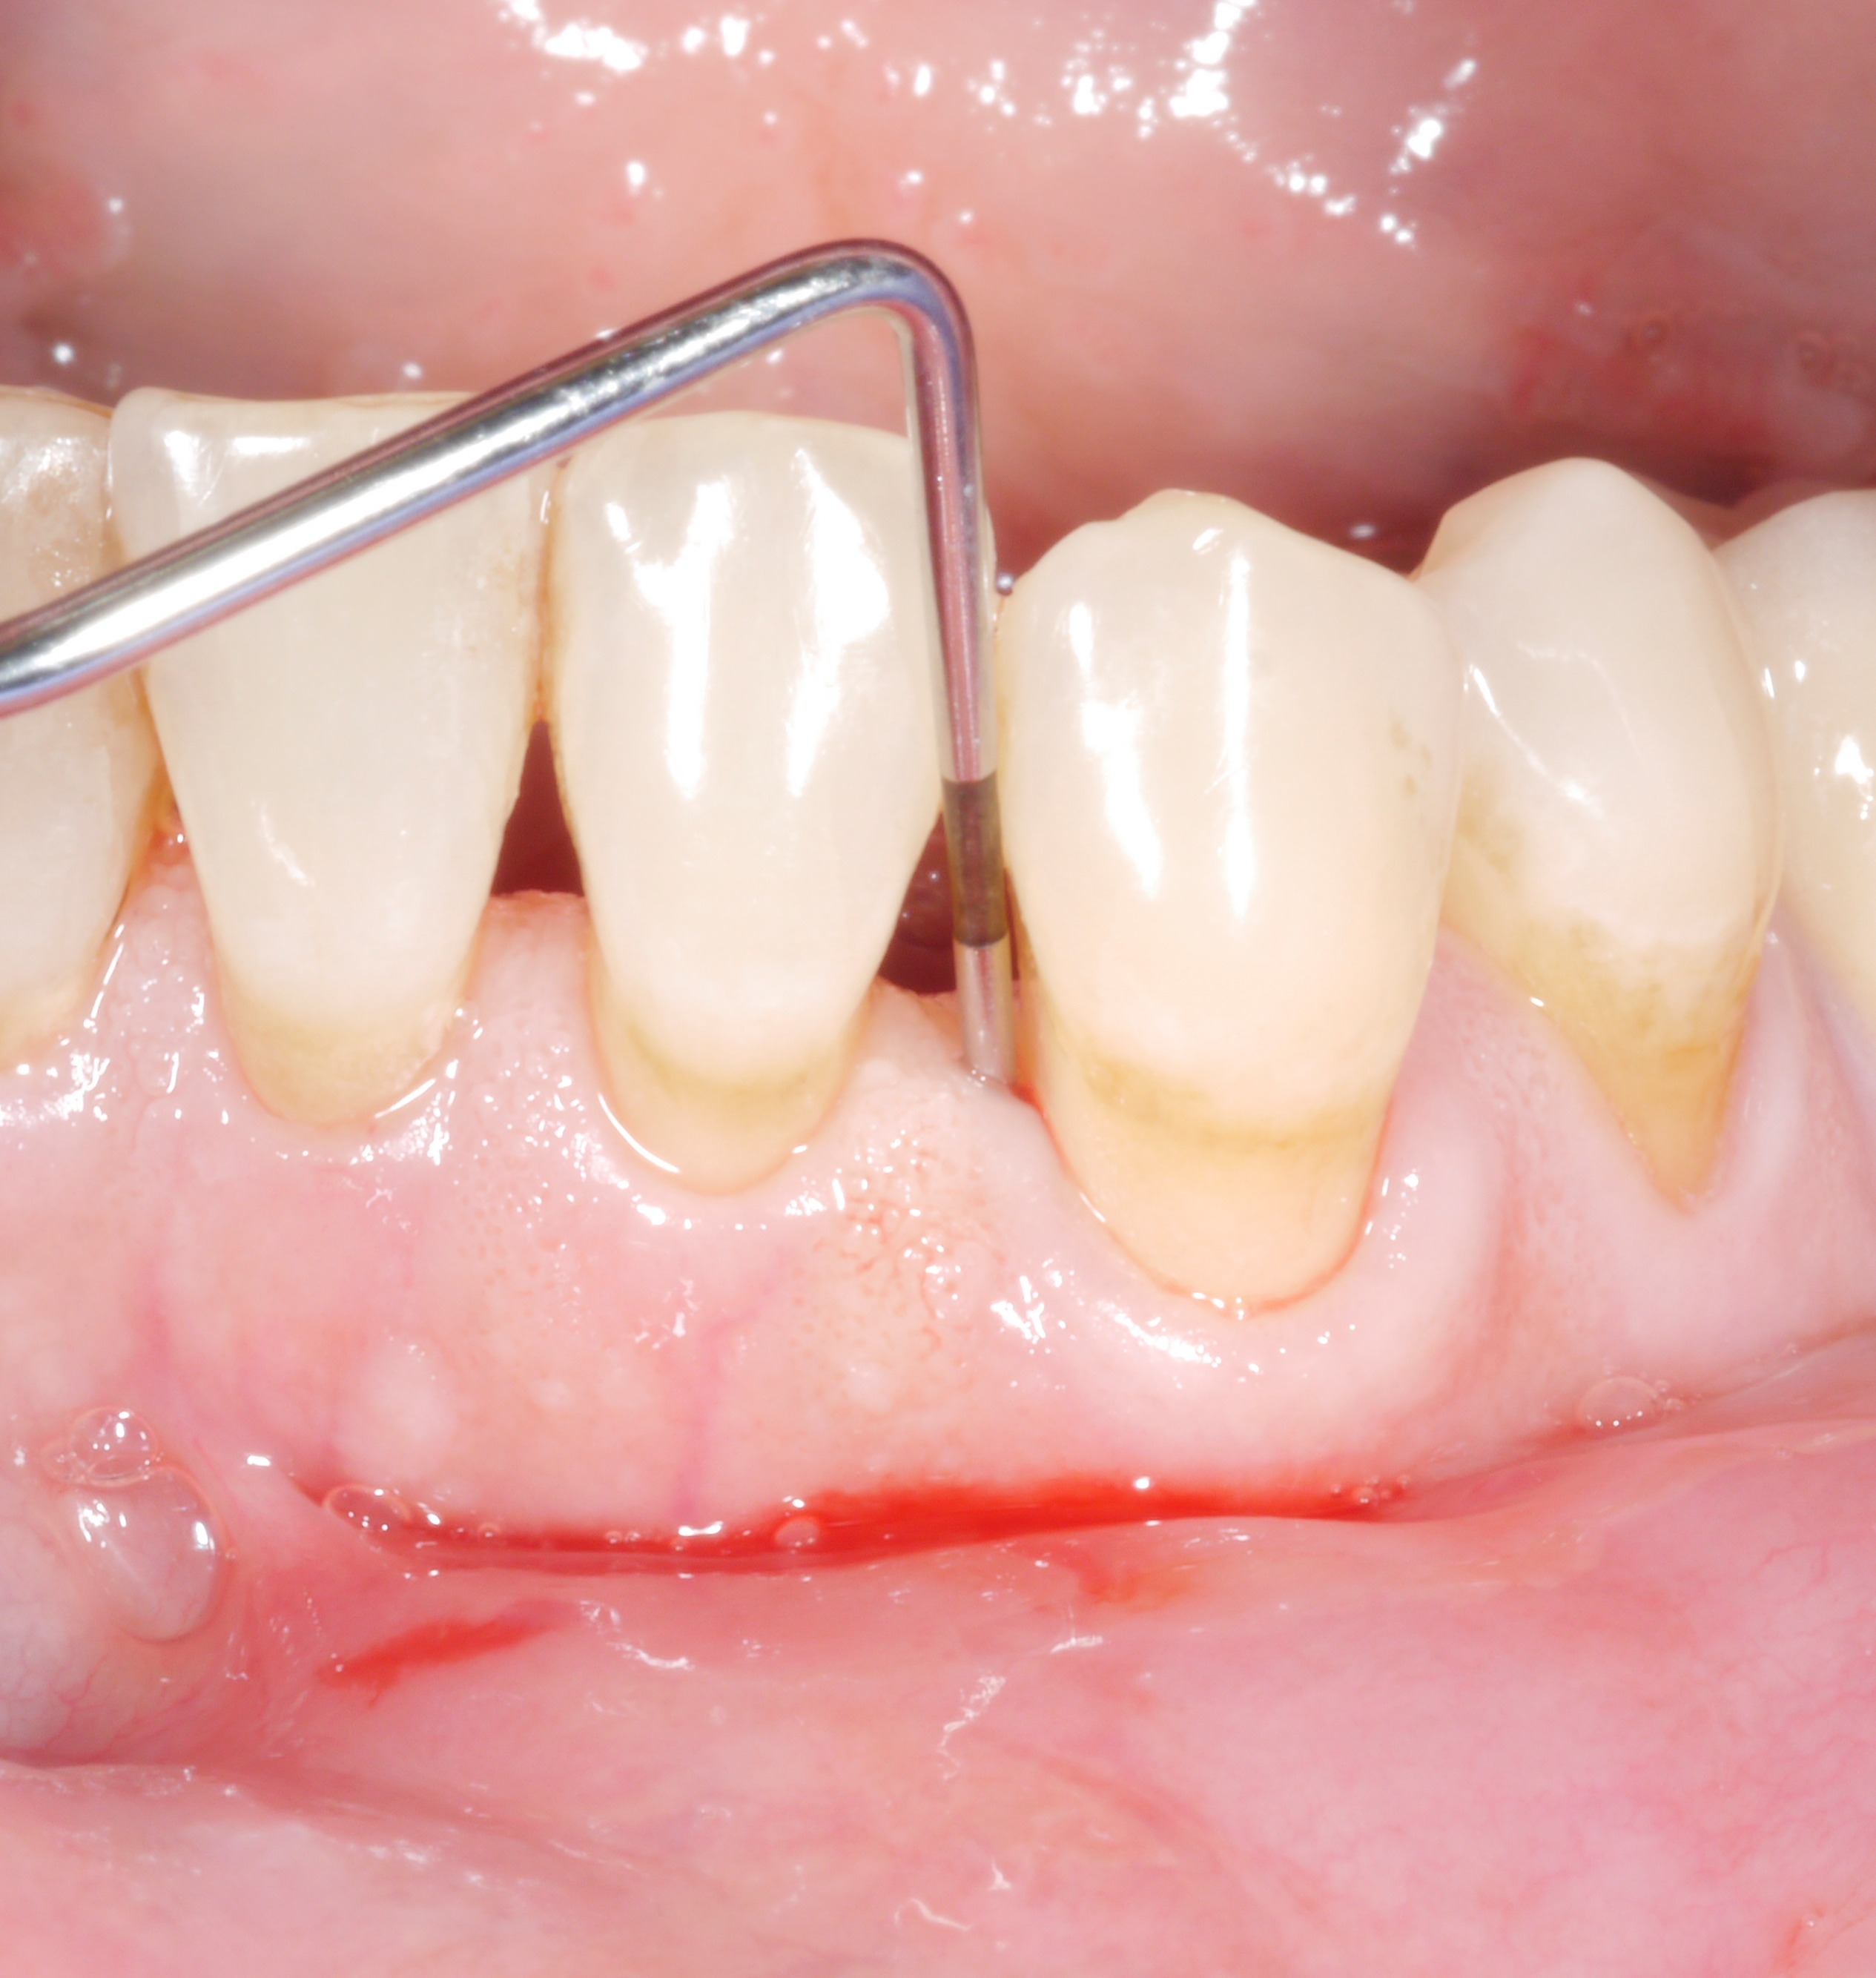

Man kennt die Situation nur allzu gut: Nach der aktiven Therapiephase weisen fast alle Zähne keine erhöhten Sondierungstiefen mehr auf, aber da sind noch diese 1 bis 2 Stellen, wo man das Therapieziel leider nicht erreichen konnte. Da liegt der Gedanke nahe: „Wie schlimm kann das schon sein? Eine einzelne Tasche mit 6 oder 7 mm – das kann doch keinen wesentlichen Unterschied machen …?“

Man sollte sich jedoch bei verbliebenen Sondierungstiefen nicht zu schnell zufrieden geben, denn bereits einzelne Restsondierungstiefen von mehr als 4 mm stellen zumindest auf längere Sicht gesehen ein Problem dar – sowohl für den betroffenen Zahn als auch für die Restbezahnung!

• Blutung nach Sondieren verdoppelte das Risiko für späteren Zahnverlust.